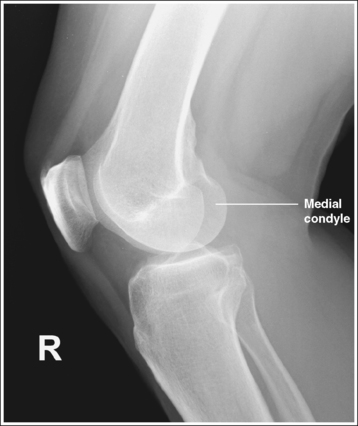

The knee demonstrates an AP projection. The medial and lateral femoral epicondyles are in profile, the femoral condyles are symmetrical, the intercondylar eminence is centered within the intercondylar fossa, and the tibia is superimposed over 0.25 inch (0.6 cm) of the fibular head.

• To obtain an AP knee projection, place the patient in a supine position with the knee fully extended. Internally rotate the leg until an imaginary line drawn between the medial and lateral femoral epicondyles is positioned parallel with the IR (Figure 6-71). This positioning places the medial and lateral femoral epicondyles at equal distances from the IR as well as medially and laterally in profile, respectively. It also centers the intercondylar eminence within the intercondylar fossa and draws the fibular neck and a portion of the fibular head from beneath the tibia.

• Effect of rotation. If the femoral epicondyles are not positioned parallel with the IR, an AP projection has not been obtained. If the patient's leg was not internally rotated enough to place the epicondyles at equal distances from the IR, they are not in profile, the medial femoral condyle appears larger than the lateral condyle, and the tibia is superimposed over more than 0.25 inch (0.6 cm) of the fibular head (see Image 54). If the patient's leg was internally rotated more than needed to place the femoral epicondyles at equal distances from the IR, the epicondyles are not demonstrated in profile, the lateral femoral condyle appears larger than the medial condyle, and the tibia is superimposed over less than 0.25 inch (0.6 cm) of the fibular head (see Image 55).

The knee joint space is open, the anterior and posterior condylar margins of the tibia are superimposed, the intercondylar eminence and tubercles are demonstrated in profile, and the fibular head is demonstrated approximately 0.5 inch (1.25 cm) distal to the tibial plateau.

• The anterior and posterior condylar margins of the tibia are superimposed if the correct central ray angulation, as determined by the patient's upper thigh and buttocks thickness, is used. By studying the tibial plateau region, you will see that the tibial plateau slopes distally approximately 5 degrees from the anterior condylar margin to the posterior condylar margin on both the medial and lateral aspects (Figure 6-72). Only if the central ray is aligned parallel with the tibial plateau slope is an open knee joint space obtained.

• Determining the central ray angulation. When a patient is placed in a supine position, the degree and direction of the central ray angulation required depend on the thickness of the patient's upper thigh and buttocks. This thickness determines how the lower leg and the tibial plateau align with the IR. Figure 6-73 shows a guideline that can be used to determine the central ray angulation for different body sizes; it illustrates the relationship of the tibial plateau to the imaging table as the patient's upper thigh thickness increases. Note that a decrease occurs in femoral decline, and a shift occurs in the direction of the tibial plateau slope as the thickness of the thigh decreases. Because of this plateau shift, the central ray angulation must also be adjusted to keep it parallel with the plateau and to achieve an open knee joint. For optimal AP knee projections, measure from the patient's anterior superior iliac spine (ASIS) to the imaging table on either side to determine the central ray angulation to use for each knee examination. When measuring this distance, do not include the patient's abdominal tissue. Keep the calipers situated laterally next to the ASIS. If the measurement is less than 18 cm, a 5-degree caudal angle should be used. If the measurement is 19 to 24 cm, a perpendicular beam should be used. If the measurement is greater than 24 cm, a 5-degree cephalad angle should be used. Using the correct central ray angulation not only results in an open knee joint space but also provides optimal demonstration of the intercondylar eminence and tubercles without foreshortening.

• Analysis of joint space narrowing. On an AP knee projection with adequate positioning, joint space narrowing is evaluated by measuring the medial and lateral aspects of the knee joint, which are also referred to as compartments. The measurement of each of these compartments is obtained by determining the distance between the most distal femoral condylar surface and the posterior condylar margin of the tibia on each side. Comparison of these measurements with each other, with measurements from previous images, or with measurements of the other knee determines joint space narrowing or a valgus or varus deformity. In a valgus deformity the lateral compartment is narrower than the medial compartment; in a varus deformity the medial compartment is narrower (see Images 56 and 57). Precise measurements of the compartments are necessary to ensure early detection of joint space narrowing and are best obtained when the knee joint space is completely open. If an inaccurate central ray angulation was used for an AP knee projection, the knee joint is narrowed or obscured, the intercondylar eminence and tubercles are foreshortened, and the tibial plateau is demonstrated.